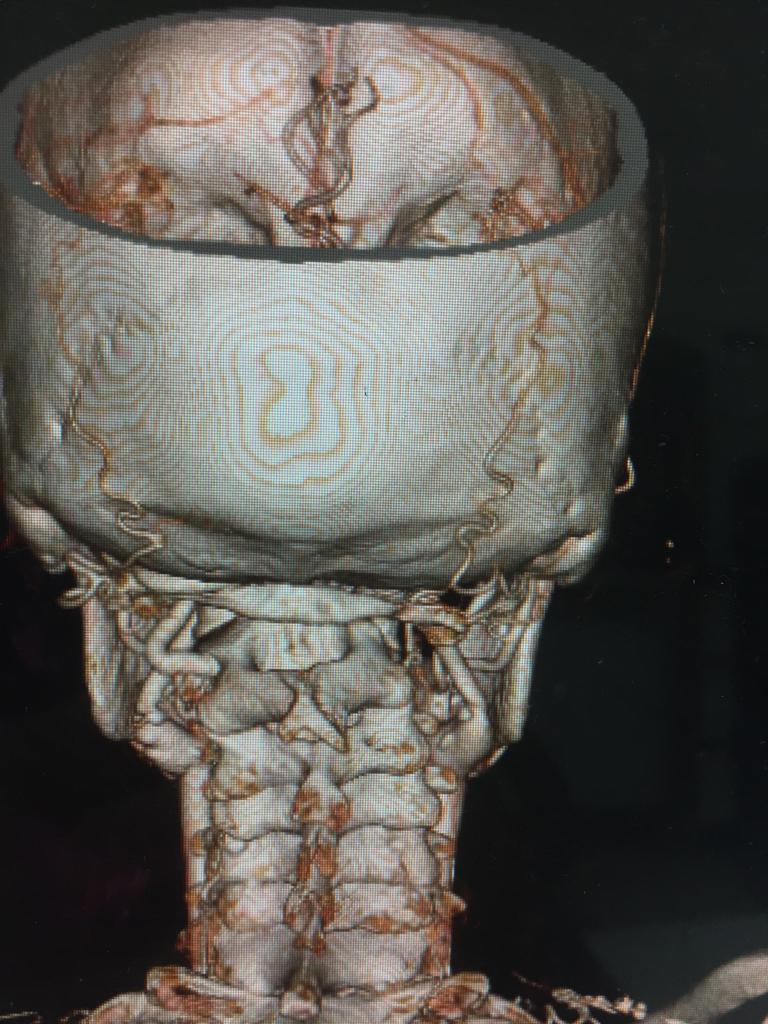

Cases